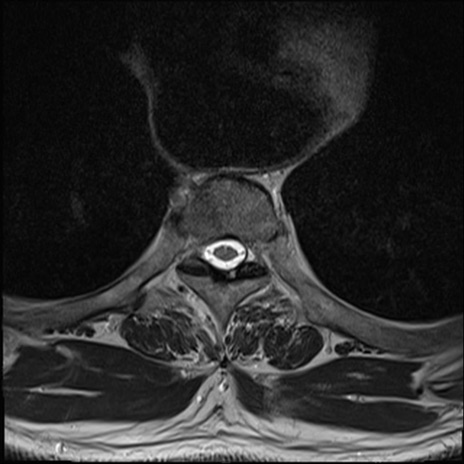

【整形】TIPS症例7 頚椎MRI T2WI(横断像)

頚椎MRI

矢状断像と横断像